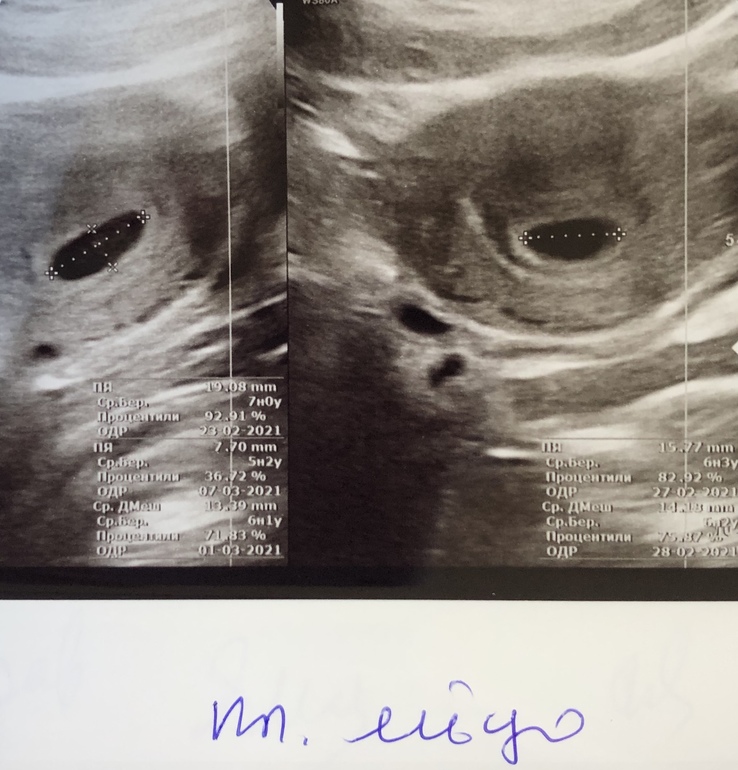

Плодное яйцо 14 мм, идём по верхней границе нормы 👌🏻

Желточный мешочек 2,9 мм

Эмбрион виден, КТР 2,8 мм.

Хорион круговой

Тонус матки обычный, шейка до 30 мм.

Жёлтое тело в ПЯ 19 мм